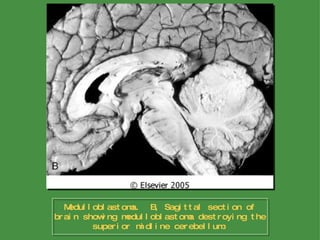

Poorly Differentiated Neoplasms Medulloblastoma In children, medulloblastomas are located in the midline of the cerebellum, but lateral locations are more often found in adults Rapid growth may occlude the flow of CSF, leading to hydrocephalus The tumor is often well circumscribed, gray, and friable and may be seen extending to the surface of the cerebellar folia and involving the leptomeninges Morphology

Medulloblastoma.  B, Sagittal section of brain showing medulloblastoma destroying the superior midline cerebellum.